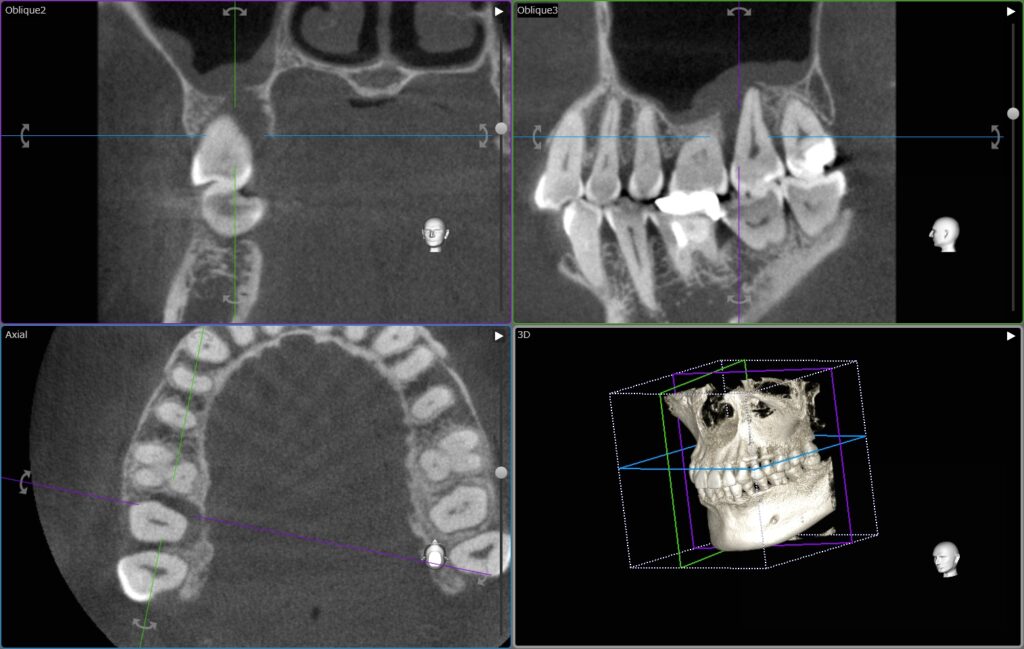

CT撮影を行うと、歯、骨が立体で描かれます。

また同時に、1本1本の歯をいろんな方向から見ることができます。

今回の右上の歯でいうと、

オレンジでマークしたところが黒く染まっているのがお分かりいただけるかと思います。

本来は白色〜鼠色で描かれ、骨があるべき部位です。

患者さんにも一目でお分かりいただけます、状態がわかれば、治療もスムーズに進みます。